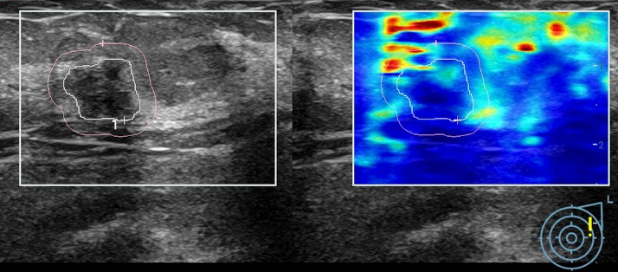

刘女士听从了我的建议,重新做了加入了超声弹性成像技术的彩超。结果确实令人担心:右乳肿物:BI-RADS 4b类(中度可疑恶性);左乳肿物:BI-RADS 4a类(低度可疑恶性);右侧腋窝淋巴结异常肿大。尽管钼靶报告提示“BI-RADS 3类”,刘女士提出质疑:“钼靶不是说没事嘛?”,我仍旧坚定的建议她:“必须穿刺!

左侧乳腺彩超+弹性成像(BI-RADS 4a类)